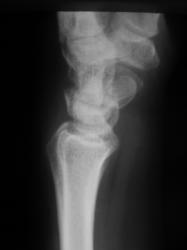

Катенёв Валенти... Дата публикации 15.10.2009, 20:32 Травма неделю тому. Пациент направлен на рентгенологическое исследование лучезапястного сустава с диагнозом "Перелом". Произведено исследование. Ваше мнение коллеги? Чт, 15/10/2009 - 20:36 #1 В.Б. Серов Не на сайте Был на сайте: 3 недели 3 дня назад Зарегистрирован: 16.07.2008 - 10:15 Публикации: 1376 Нужен косой снимок, подтвердить/опровергнуть перелом ладьи. Зри в корень! Чт, 15/10/2009 - 21:37 #2 Наталия Не на сайте Был на сайте: 9 лет 2 недели назад Зарегистрирован: 30.07.2008 - 13:24 Публикации: 538 Перелом ладьевидной кости без смещения виден хорошо. Чт, 15/10/2009 - 21:53 #3 Катенёв Валенти... Не на сайте Был на сайте: 7 лет 5 месяцев назад Зарегистрирован: 22.03.2008 - 22:15 Публикации: 54876 Да. линия перелома в ладьевидной кости, весьма хорошо дифференцируется

Перелом ладьевидной кости без смещения виден хорошо.

Да. линия перелома в ладьевидной кости, весьма хорошо дифференцируется